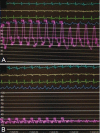

Figures